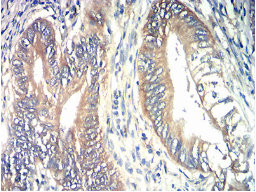

TIA1 Mouse Monoclonal antibody[3A3B9]

IHC    1/200-1/1000